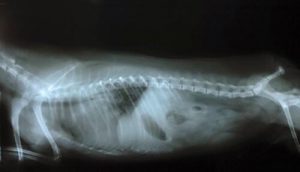

Die Differentialdiagnose des Wobbler-Syndroms erfolgt durch Beobachtung der Wirbelsäule und der Wirbel. Zu diesem Zweck wendet der Tierarzt Röntgen, CT, MRT und Myelographie an.